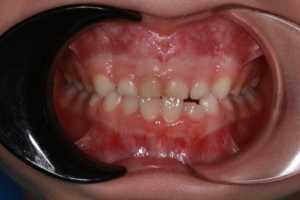

Достаточно часто при лечении на аппарате Хааса мы наблюдаем положительные изменения и на нижней челюсти, хотя никаких конструкций для неё не использовали. Почему так происходит?

У детей в период активного роста очень хорошо проходит саморегуляция и когда нижняя челюсть высвобождается из «оков» маленькой и узкой верхней, она реализует свои потенциалы физиологического роста, расширяется, положение зубов улучшается.